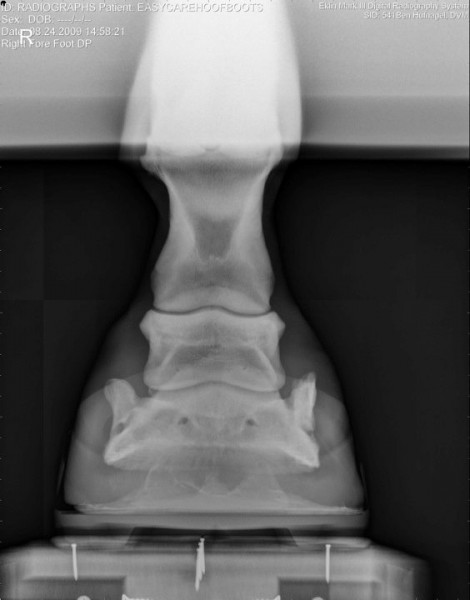

Společnost EasyCare si dělá vlastní průzkumy-výzkumy… zde jsou zajímavé fotografie jak to vypadá když je kopýtko v botě, zůstává ve svém přirozeném tvaru, kopytní mechanismus je neomezený a kůň ho má možnost plně přirozeně využívat 🙂